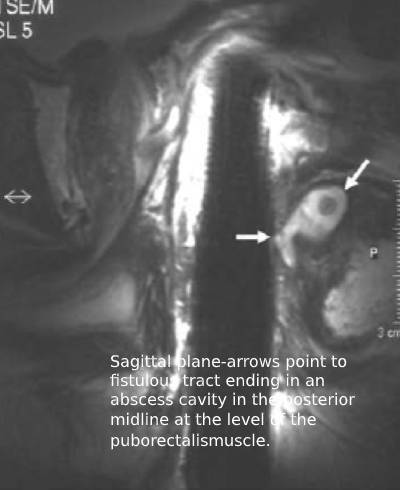

- MRI is the investigation of choice for anorectal abscess.

MRI scan is especially useful when there are no external signs of, but a high index of suspicion of anorectal abscess. It is also indicated in a complex fistulous abscess.